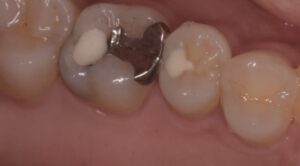

また、大きく削って被せ物をしないと治療報酬的に赤字になるということで、本当に大事な部分を削っては金属で被せてきました。歯を守るための理論を完全に無視した治療(破壊行為?)が平然と行われているのが現状です。そうしないと医院経営ができないような健康保険のシステムが悪いと考えていますが、安かろう悪かろうで通用していました。その結果、上の写真のように、被せ物の縁からは細菌がドバドバ入り、外すと歯がボロボロという悲しい状況がつくられてしまいました。被せ物は丈夫なので、外からはわからないけど、中は腐ってグジュグジュ、という歯を何千本見てきたことでしょう

他院で治療をしてもらったが、痛みがずっと続く、ということで当院に来られました。診査の結果、右上6番目の歯の神経が細菌感染を起こしているため、痛みが続いているとわかりました。そこで、2回に分けて、根管治療と修復処置を行いました。

横の右上5番目の歯は神経近くまで虫歯は進んでいましたが、神経を保存することが出来ました。

このまま少なくとも1年以上は経過をみて、問題がないかを確認する必要がありますが、現状は痛みもなく噛めているとのことで治療は無事に終了となりました。